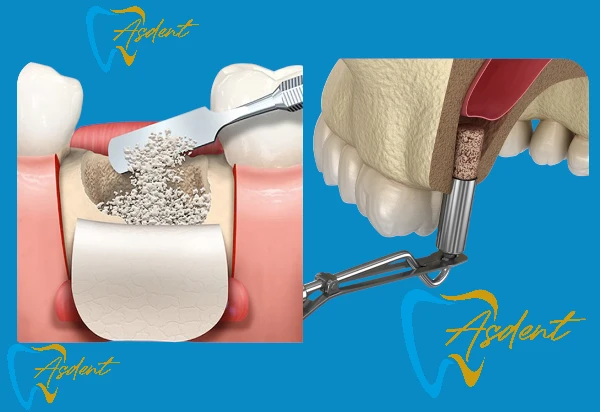

Kemik Grefti ve Sinüs Kaldırma + İmplant Paketi /ASDENT Bursa İnegöl

• Kemik hacmi yetersiz olan hastalar için özel çözüm

• Kemik grefti, membran ve sinüs kaldırma prosedürü

• Ardından implant yerleştirme

• Takip, ilaçlar ve iyileşme süreci izleme dahil.

Avantajları: İmplantlar için kemik yapısı yetersiz olan hastalar için bile kalıcı çözüm